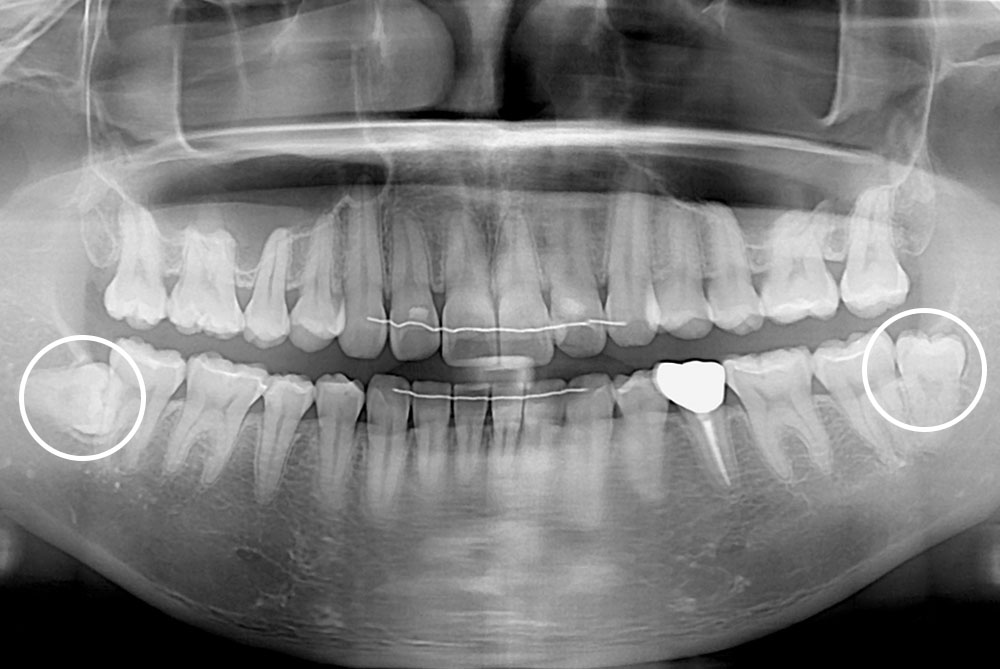

[사랑니] 매복 사랑니 발치

치료전 : 2020-02-17